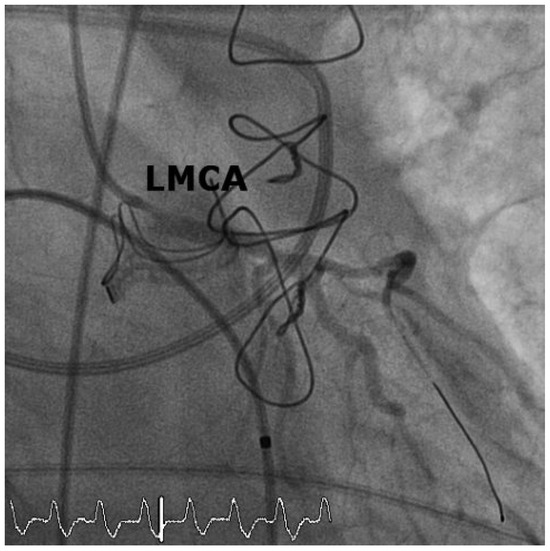

Case2